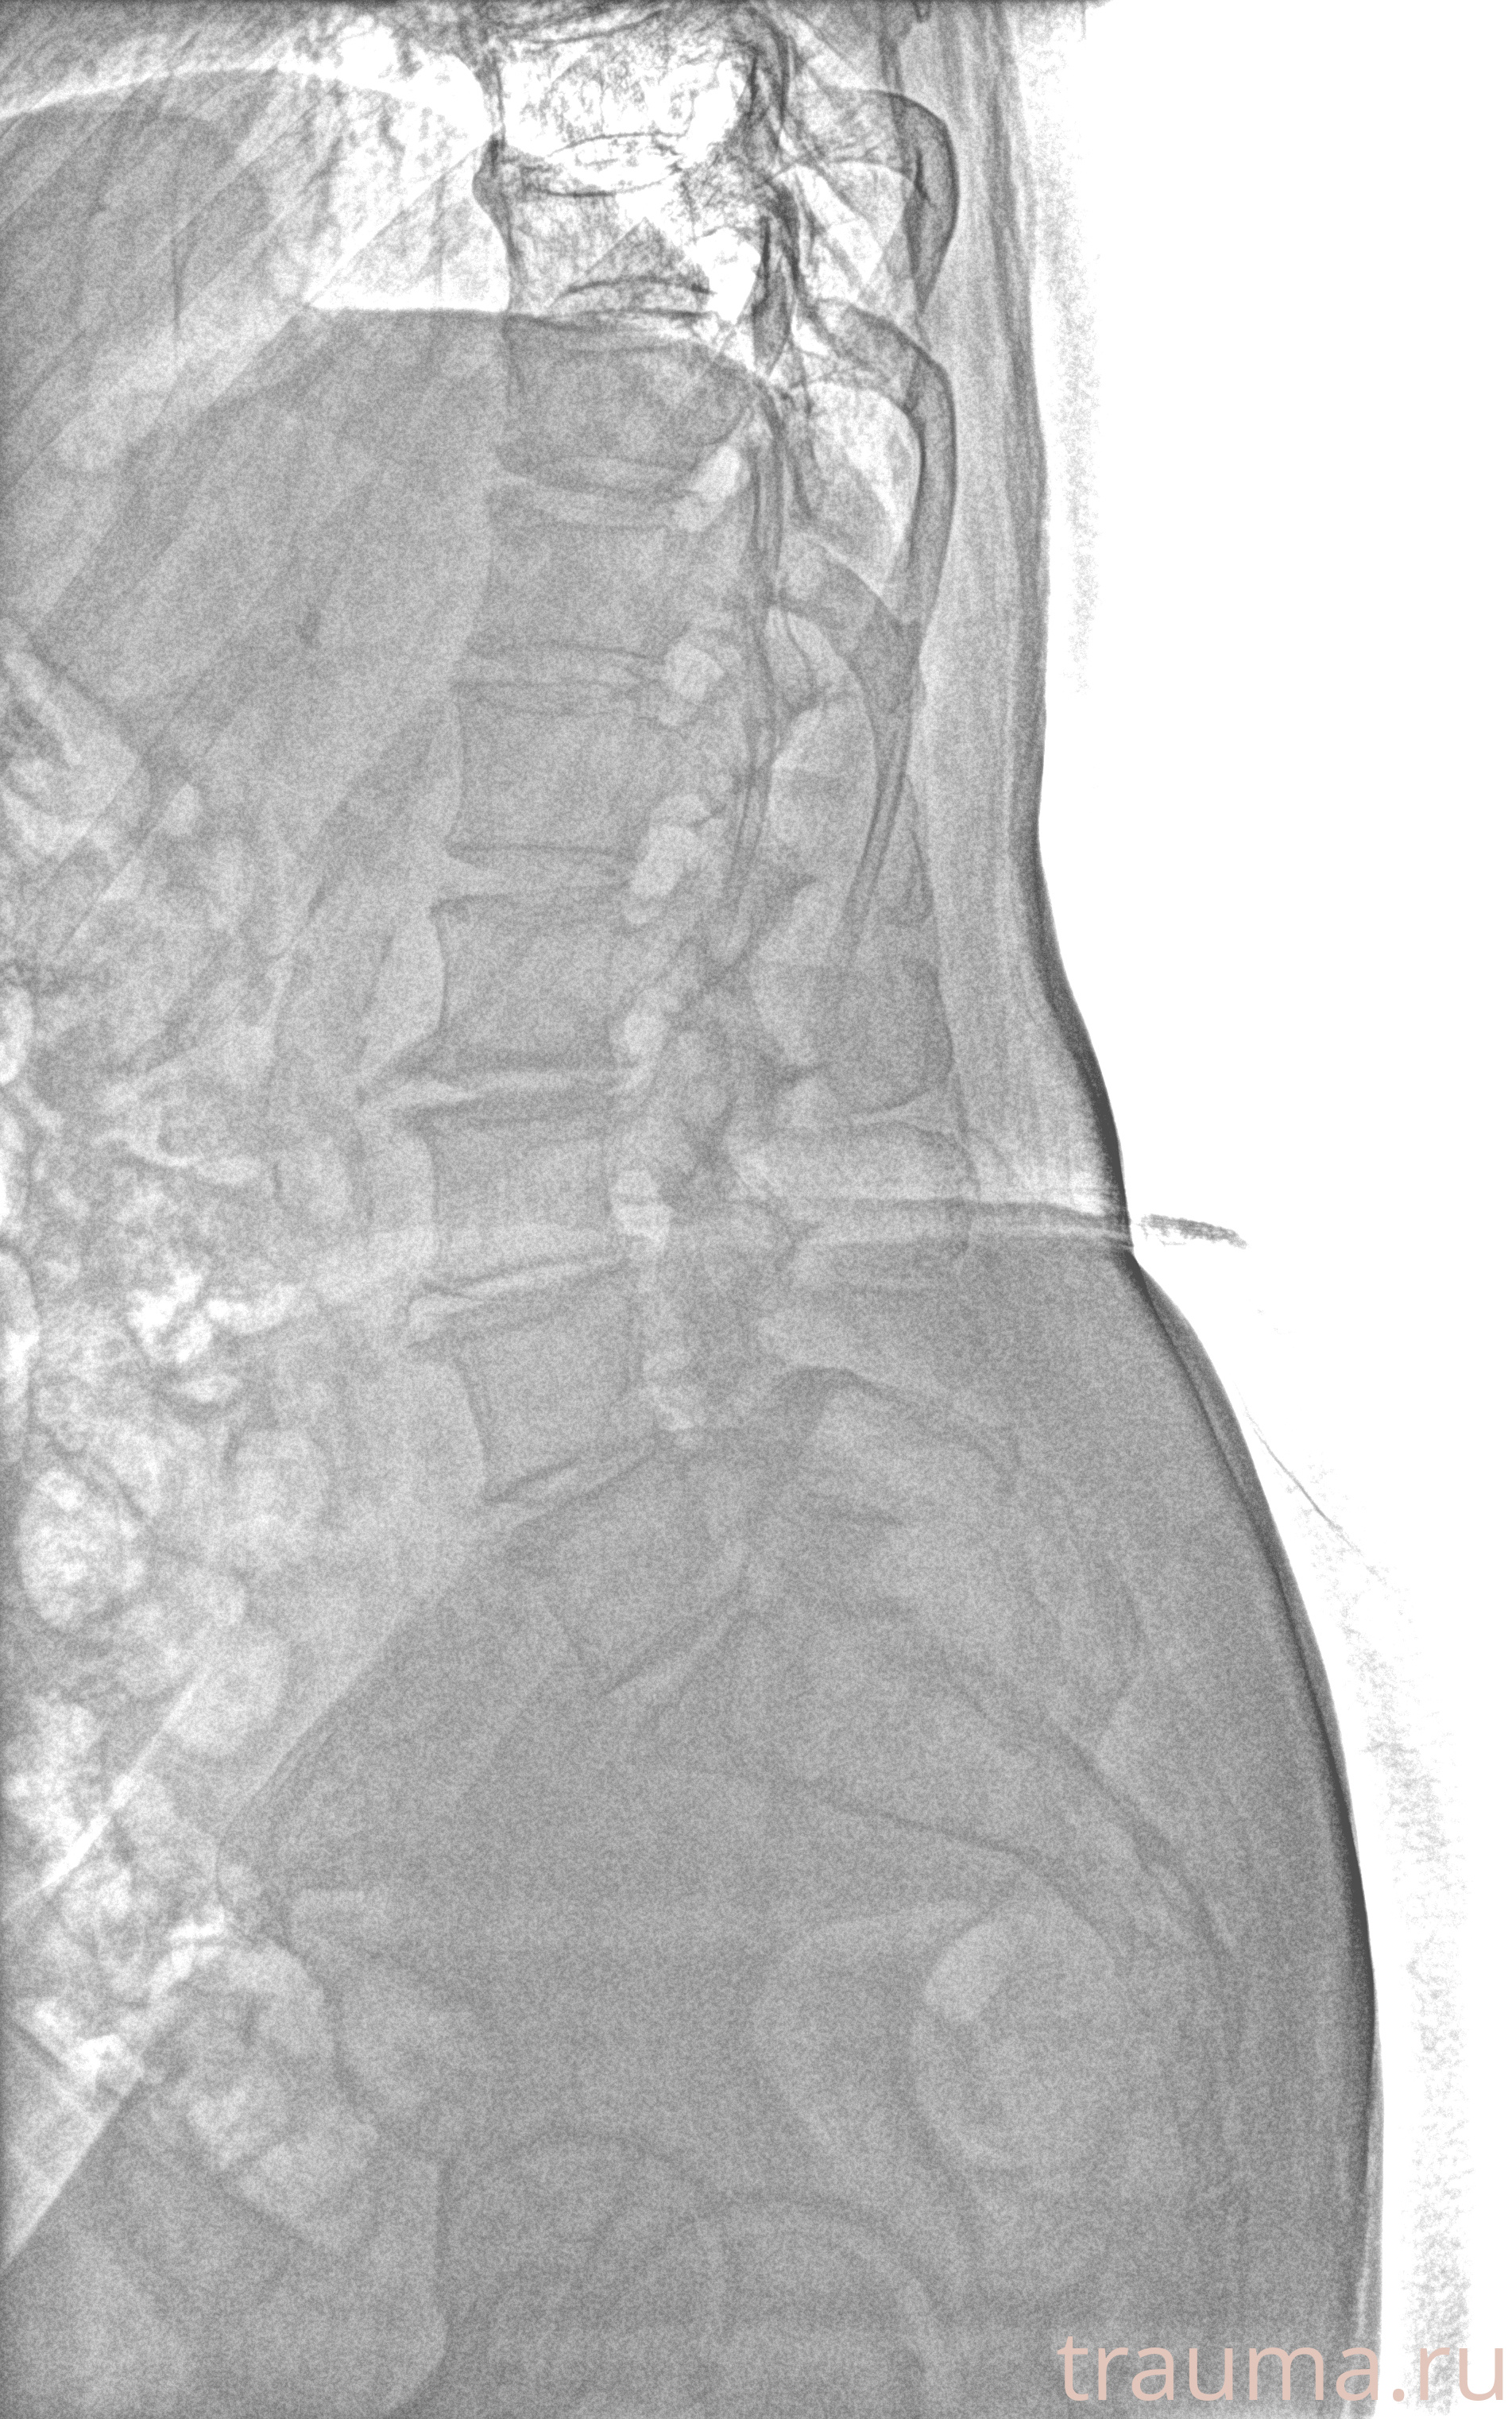

Рентген на дому: по вашему адресу приезжает врач-рентгенолог, травматолог-ортопед с мобильным рентгеновским аппаратом, проводит диагностику травмы или заболевания, делает необходимые рентгенограммы, дает рекомендации по дальнейшему лечению. Получить качественные снимки в домашних условиях возможно благодаря уникальной методике, разработанной МосРентген Центром для института  Склифосовского